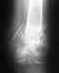

Уважаемые доктора, имеем девочек-двойняшек, полный возраст 1 год 3 месяца и 3 недели. ЕР в срок 38 недель и 5 дней, головное предлежание обеих, вес при рождении 2670 и 2640 гр. Полностью самостоятельно передвигаться начали в 1.2 года, долгое время сидели исключительно в позе W.

По вине нас родителей дети на первый прием к ортопеду попали в таком позднем возрасте, ранее со стороны педиатра, хирурга и невропатолога подозрений на дисплазию не возникало. Пару недель назад обратили внимание, что одна из дочерей начала "загребать" ногой при ходьбе. Сейчас при прокручивании слышны периодически щелчки в суставах правых ног у обеих. По направлению ортопеда сделаны снимки. 2 специалиста трактуют их по-разному и назначают лечение (в одном случае это шины Виленского на 3 месяца в дополнение к массажу и физиопроцедурам и затем контроль через 3 месяца, второй специалист говорит, что массажа и физио достаточно и контроль через 6 месяцев). Прокомментируйте пожалуйста снимки, т. к. насколько я понимаю от измеренных углов наклона и варьируется назначенное лечение. Необходимо ли в нашем случае ношение шин? Спасибо!